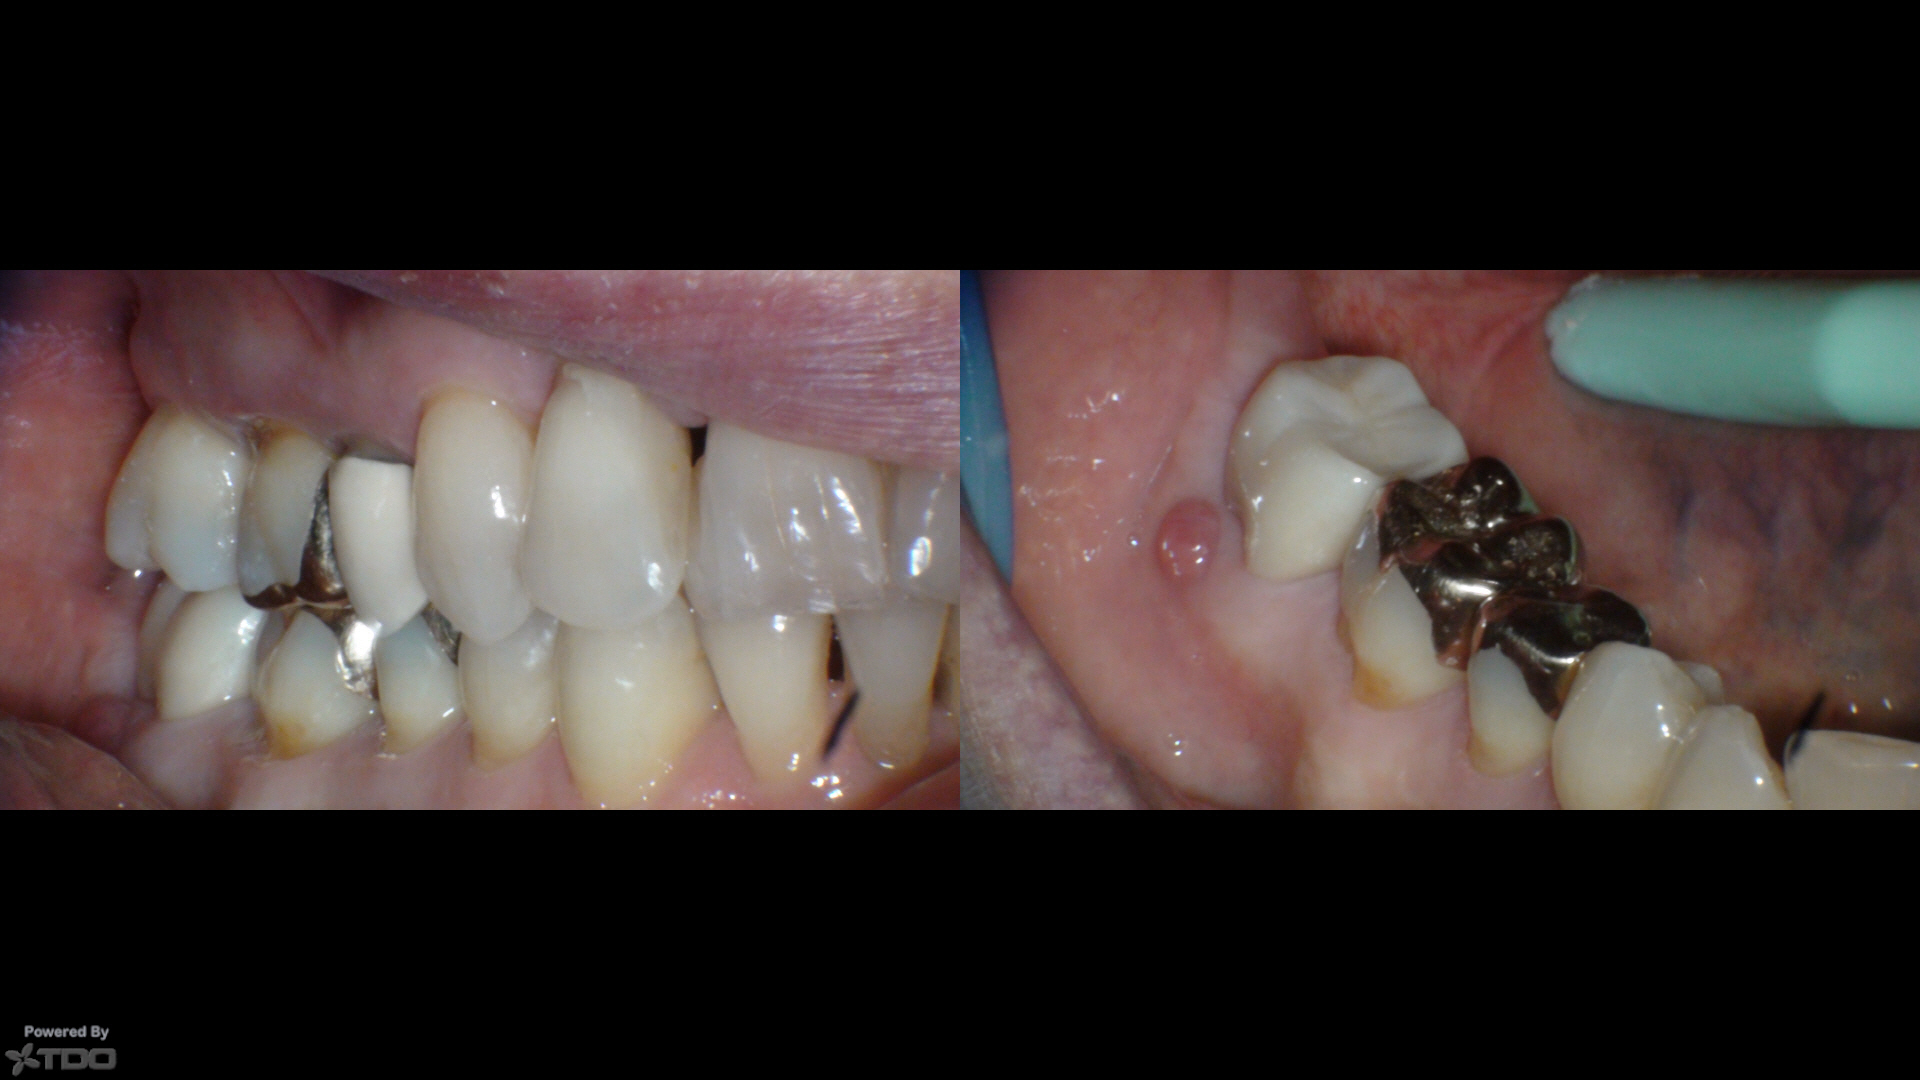

73yof in today for obvious reasons.

I just can't figure this out…let alone why anyone would be teaching it…